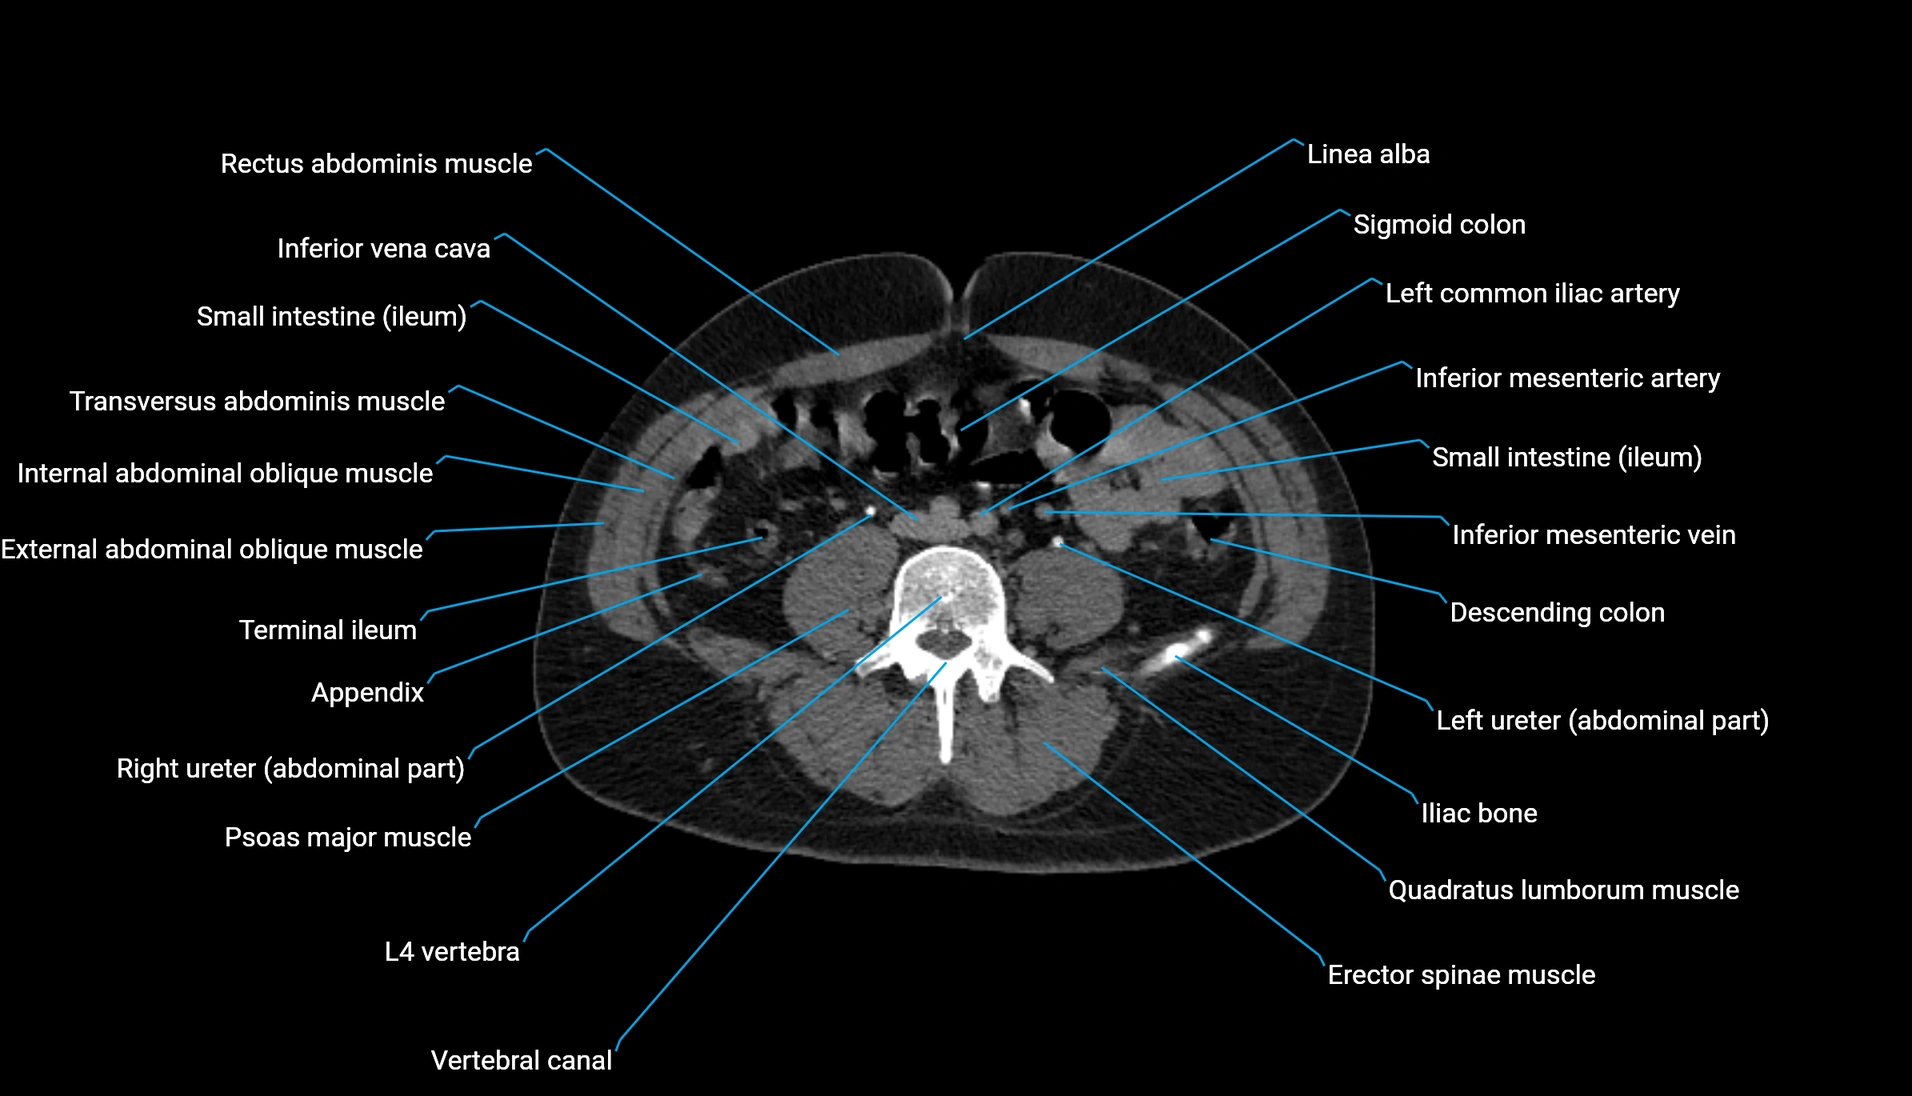

CT Appearance

Non-contrast CT:

-

Demonstrates cortical bone of acetabular rim in excellent detail

Detects fractures, dysplasia, retroversion, or bony overcoverage (pincer impingement)

3D reconstructions used in preoperative hip surgery planning

CT VRT 3D image

CT image